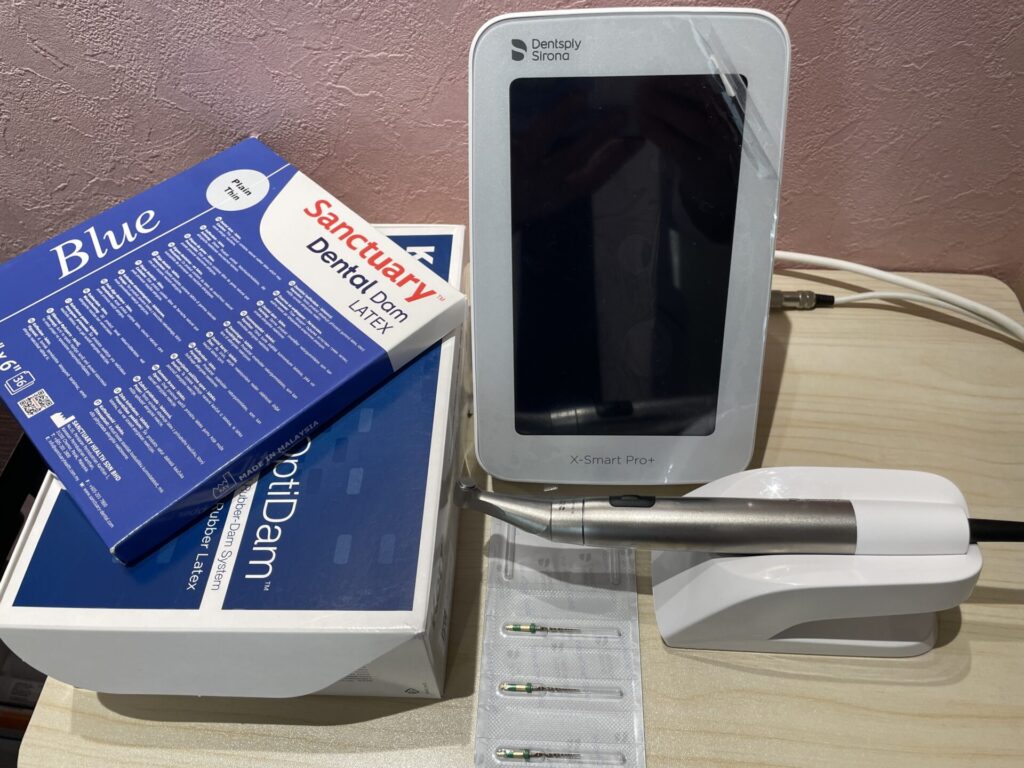

ラバーダム防湿を行い、マイクリスコープ下での治療です。近心の根には2つの根管があります。この第2根管は裸眼の治療では高頻度で見落とされる傾向にあります。CTを事前に撮影しておくことで複雑な歯の神経の道を事前に把握することは非常に重要です。

頬側の膿の出口は綺麗に治りました。また保険治療では神経治療した歯歯大きく削りクラウンという被せ物で補われますが、ご本人様のご希望にてダイレクトボンディングで歯の形を作り上げています。